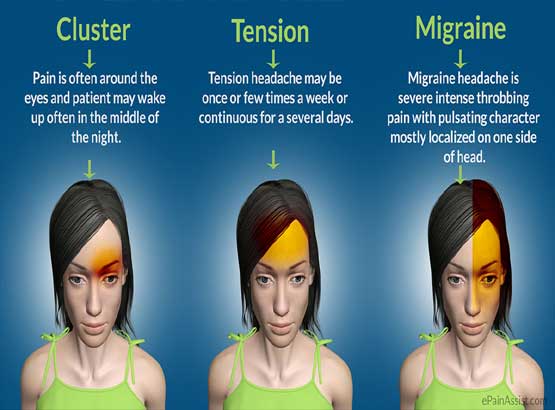

Brief profile: Dr Arghya Mukherjee, a university certified doctor for pain management with background knowledge of Anaesthesiology has been providing treatments for those affected with acute and chronic pain. Dr Arghya Mukherjee applies his expertise in a wide variety of advanced, minimally invasive procedures as part of a comprehensive approach to treat patients with acute and chronic pain.

Fields of expertise: Dr Arghya Mukherjee has special interest in Ultrasound guided acute and chronic interventional pain management procedures. He performs Fluoroscopy guided interventional pain management procedures for chronic and cancer pain as well with expertise.